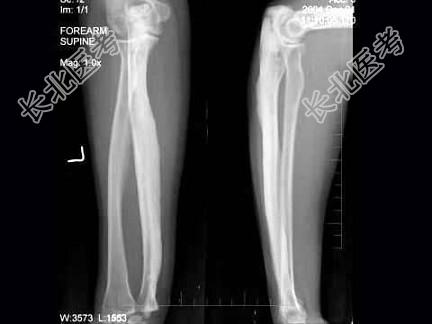

- 单项选择题30岁,女, 因左前臂酸胀不适1年,活动可, 左前臂正侧位片如图所示,最可能诊断是 ( )

A、左尺骨蜡泪样骨病

B、石骨症

C、骨皮质增厚症

D、骨膜炎

E、慢性化脓性骨髓炎